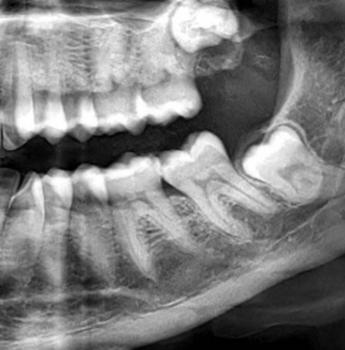

A Cone Beam Computed Tomography (CBCT) Scan is a high-tech 3D imaging system nga mas precise kaysa traditional X-rays. Makita sa dentist ang detailed structure sa imong bones, teeth, nerves, and soft tissues—perfect for:

Dental implants (exact bone measurement)

Wisdom tooth extraction (avoid nerve damage)